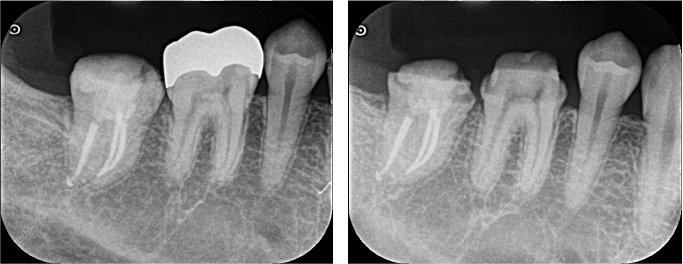

右下7番(第二大臼歯)の根の先に膿がたまっている根尖性歯周炎という状態でした。治療の選択肢として、現在入っているクラウンやメタルポスト(土台)を全て除去して、精密根管治療を行う方法が第一選択として挙げられます。しかし、今回は残存歯質量に不安がある点、古い修復物除去時に歯が割れる可能性がある点などから、通常の根管治療ではなく、意図的再植術の適応と診断しました。